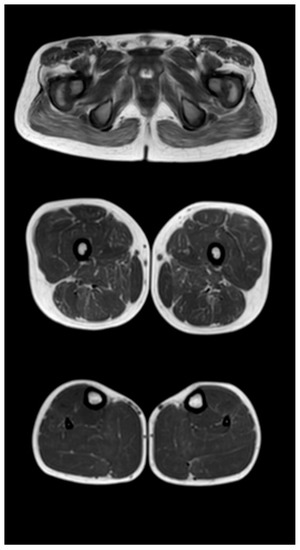

Figure 5.

Pattern of involvement of the muscles of the lower extremities in a patient at a late non-ambulatory stage of the disease (13 years). From top to bottom: the pelvic level, the femoral level, and the level of the legs.

Figure 5 shows the pattern of lower limb muscle involvement in a patient in the late non-ambulatory stage of the disease. The late non-ambulatory stage is characterized by total fibro-fatty degeneration of the muscles of the pelvic girdle, hips, and legs (stage 4). Noteworthy is the negative pattern—complete preservation of the gracilis muscle (stage 0) and the anterior muscle group of the legs—of the anterior and posterior tibial muscles (stages 2a and 1, respectively).